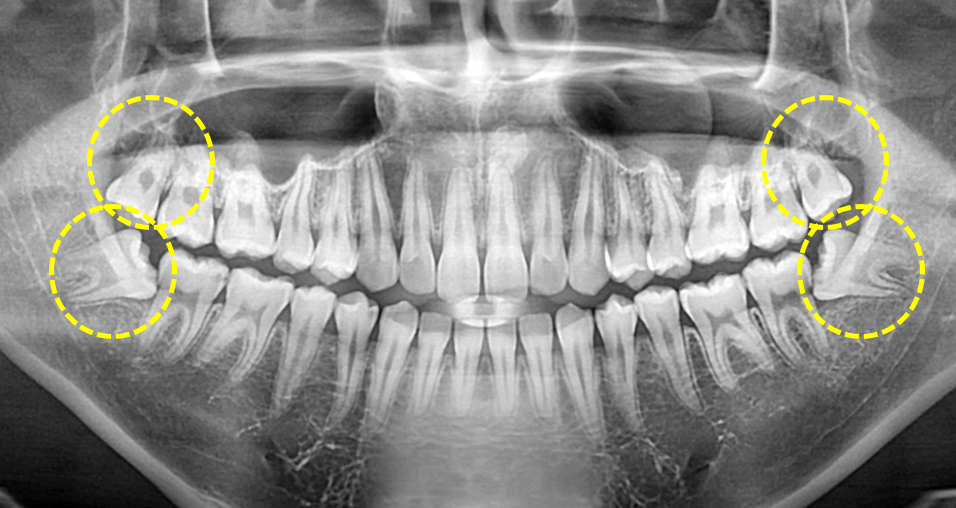

양측 상,하악 사랑니 발치.

Before

보통은 한쪽 위, 아래 사랑니를 먼저 발치하고

어느정도 치유가 이루어지면 반대편 위, 아래 사랑니를 발치하는 것이

저작과 음식물 섭취에 오는 불편을 최소화 해줄 수 있습니다.